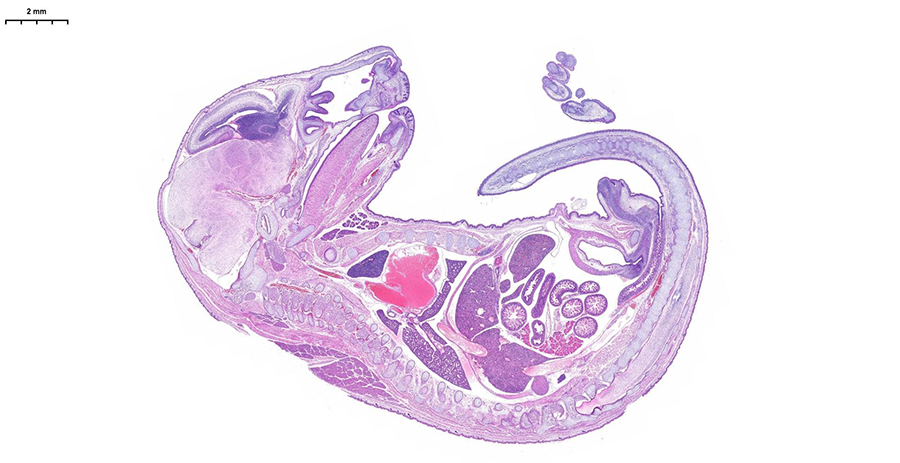

Сможете оценить высочайшее разрешение, скорость обработки (полное стекло за 3-5 минут) и интеллектуальное аналитическое ПО, которое автоматически распознаёт структуры и формирует количественные отчёты с готовыми данными. Можно принести для апробации свои образцы, демонстрируемая конфигурация флуоресцентных каналов (Ex/Em, нм):